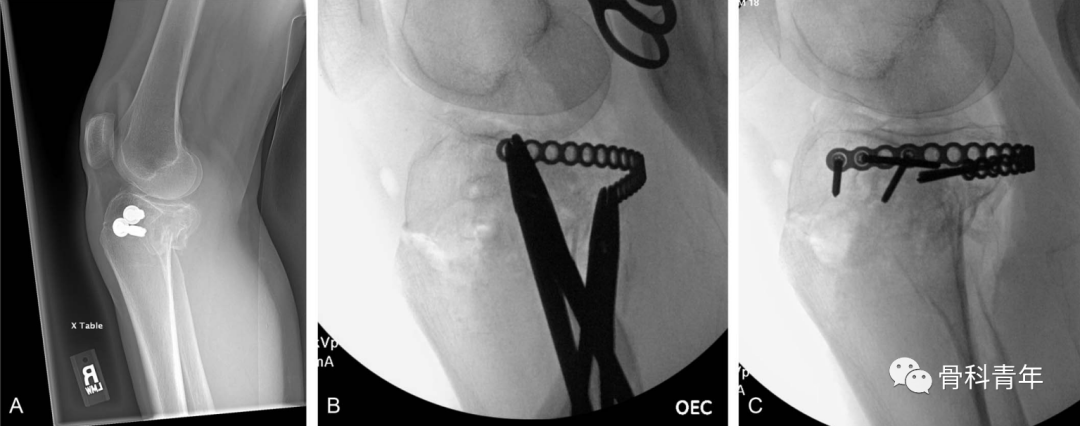

本文介绍一种仰卧位,联合前外侧入路与后内侧入路,复位后环形钢板内固定治疗累及胫骨双髁的冠状面劈裂骨折的新方法。

在复位满意后,将环形钢板塑形,通过平台后方建立的软组织隧道,穿出至外侧,并在外侧采用2枚2.7mm螺钉临时固定。

步骤4:点式复位钳拉紧环形钢板后,在内侧置入2枚2.7mm普通螺钉固定。关节面直视下及C臂机辅助下,评估复位情况及钢板位置情况。

典型病例: